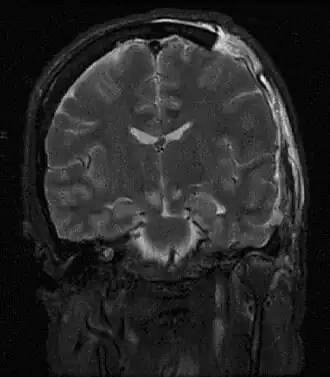

![]() МРТ, показывающая дислокацию мозга | |